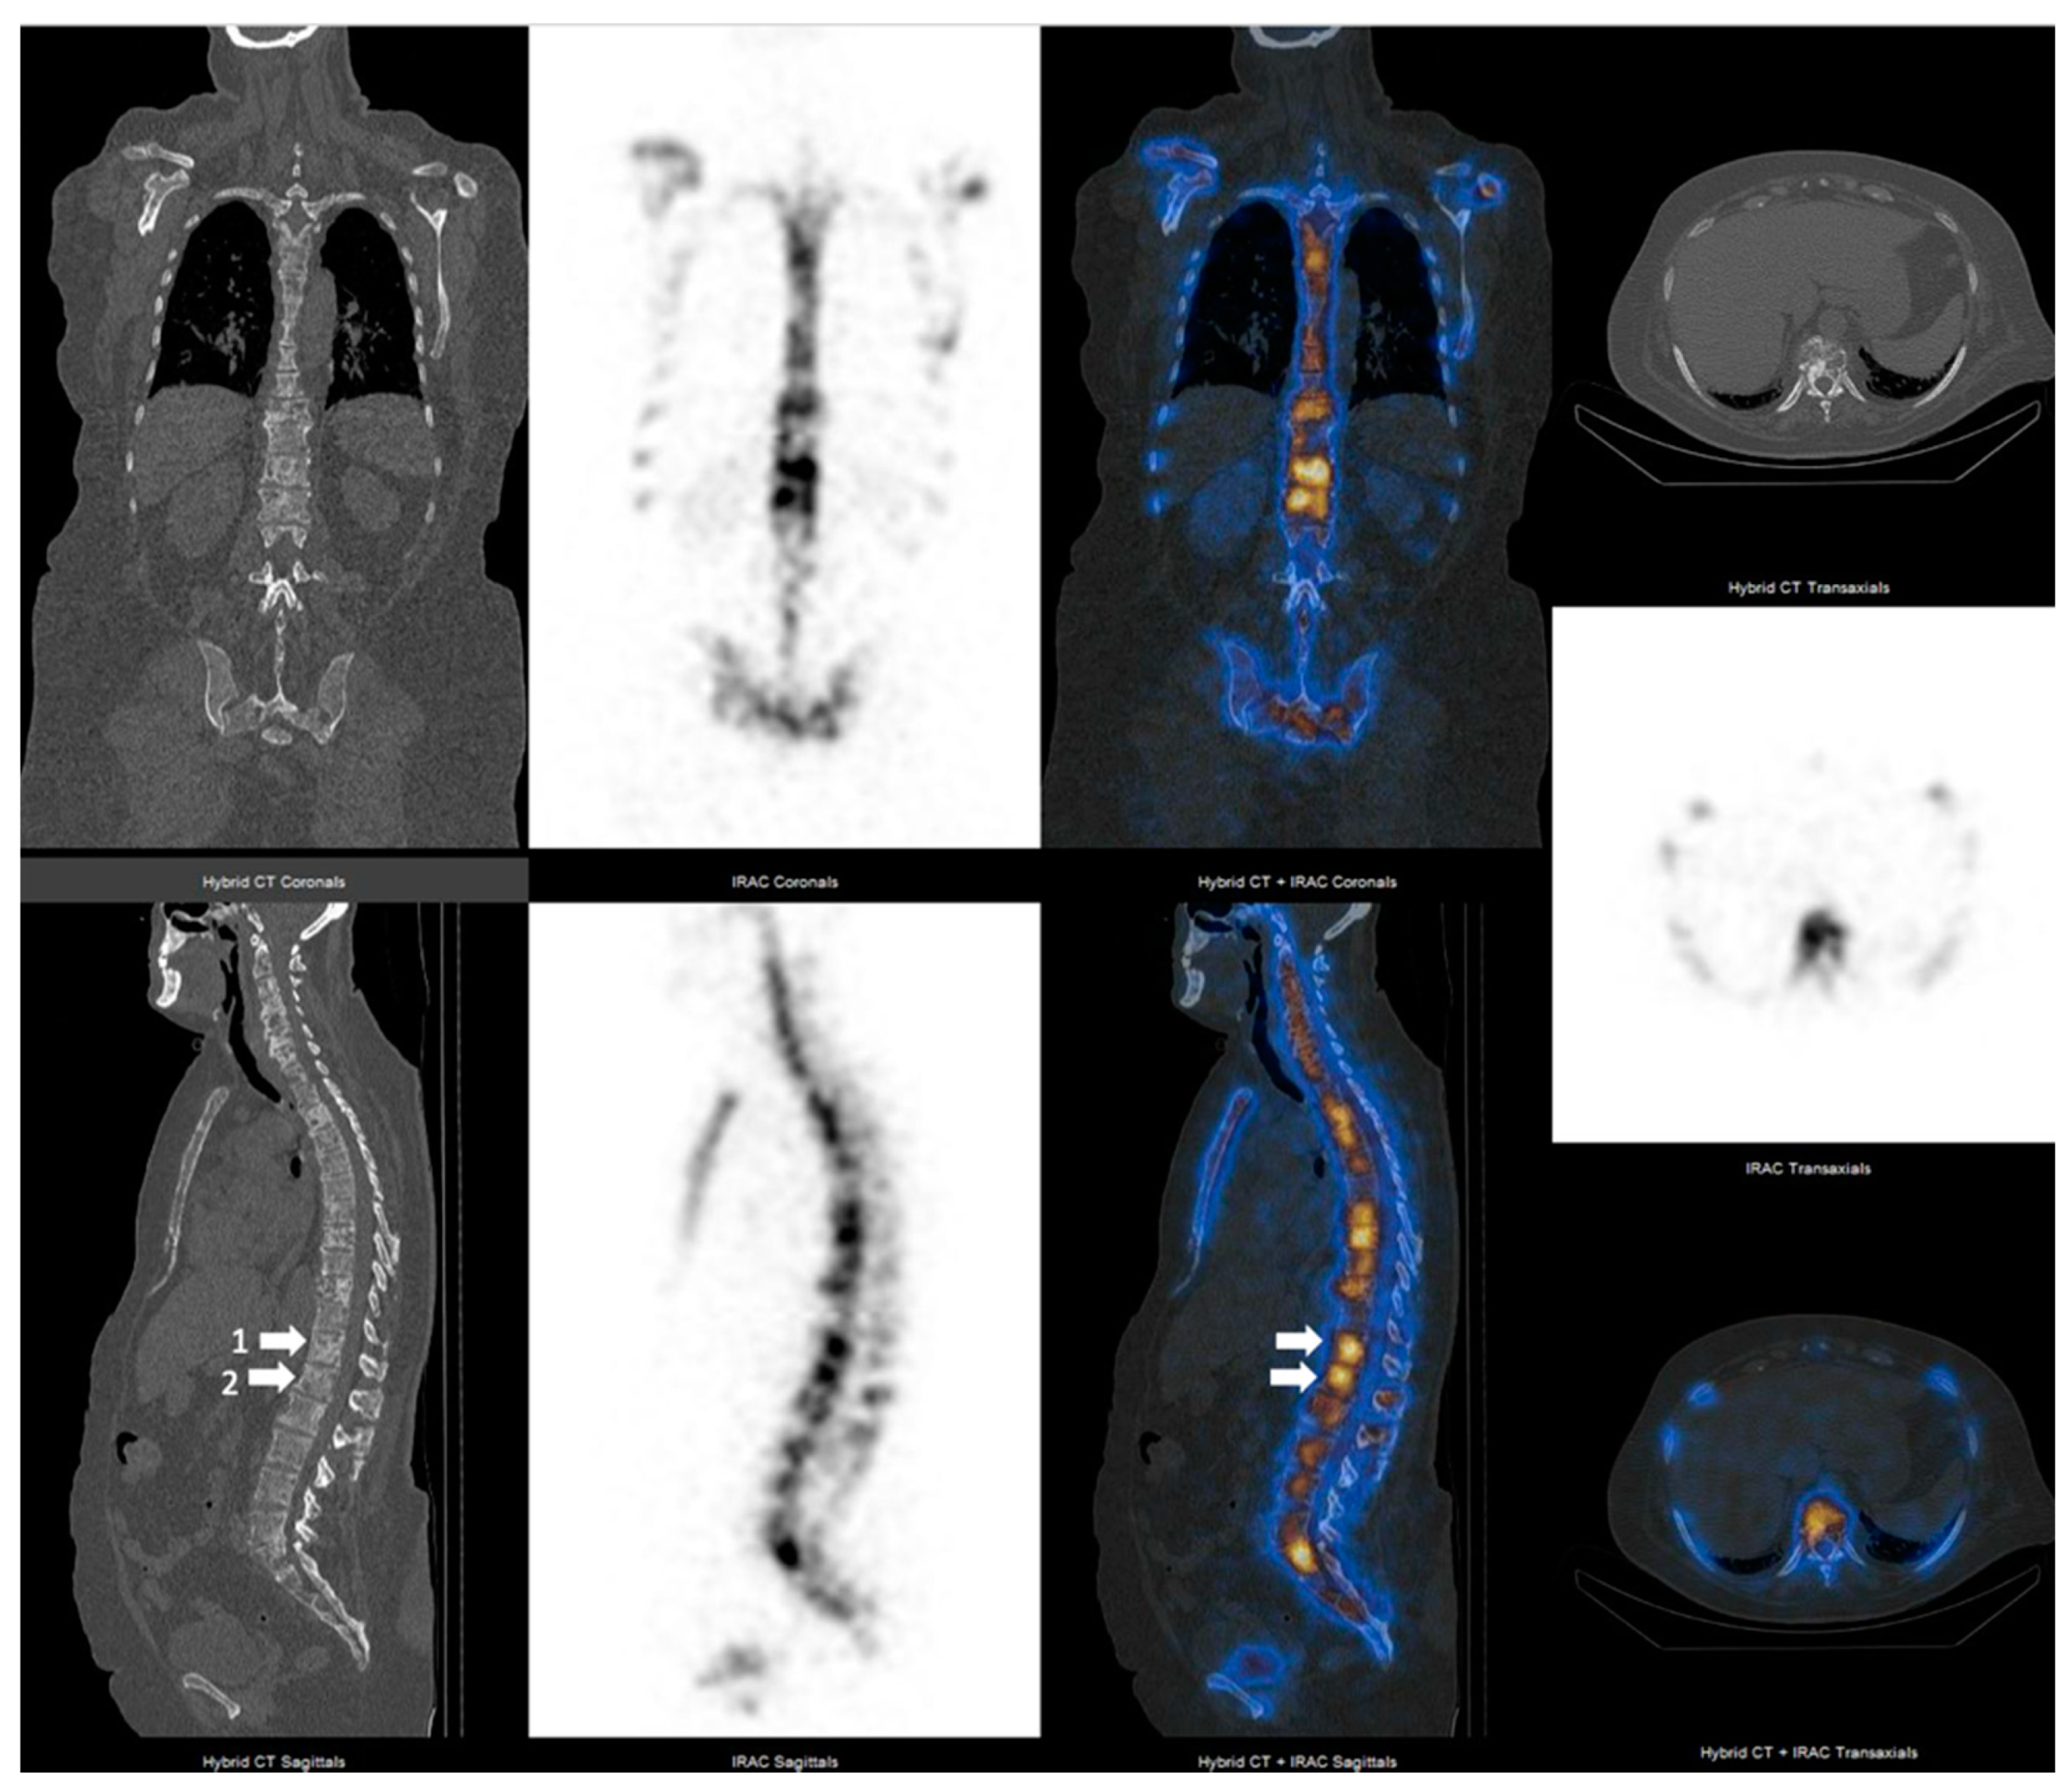

3.2. SPECT-CT SUVmax in Metastatic Lesions and Degenerative Bone Disease

3.3. SUVmax Cutt-off Value in Differentiating between Degenerative and Metastatic Lesions